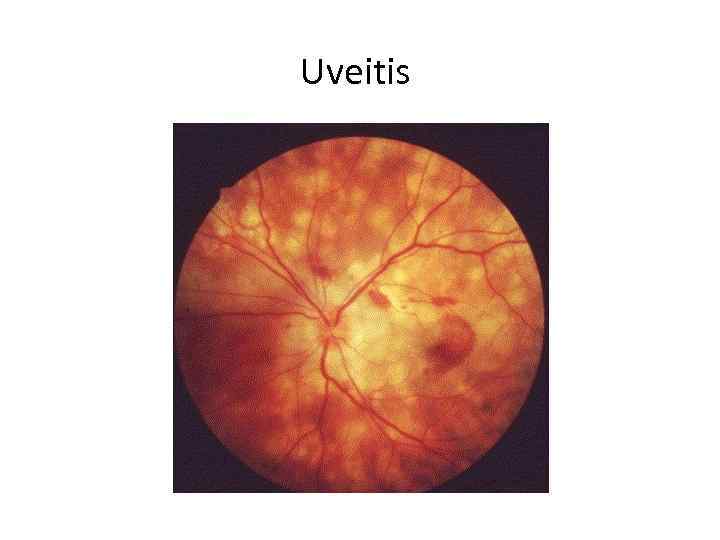

Uveitis